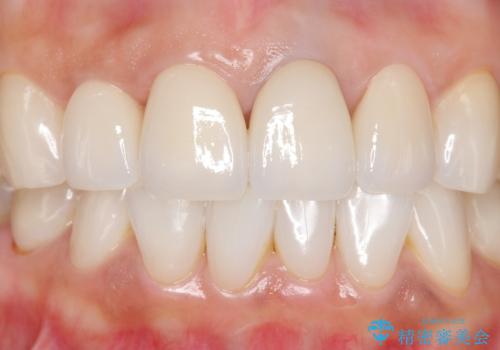

5年前のクラウン装着時と比較したところ、歯肉が成熟し歯間乳頭ができており、より天然歯のように自然に見えました。

患者様の良好なセルフケアと精密な適合の良いクラウンにより、歯肉の腫脹や退縮も認められませんでした。